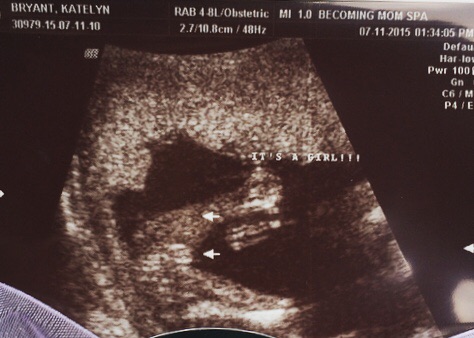

We got a private scan at 16 weeks 5 days. The ultrasound tech said she was 100% sure it was a girl. But for some reason I'm still freaking myself out. His mom has bought so many girl clothes already ( first grandchild ) I'm now 21 weeks and I go in 2 days for my anotomy / growth scan, which I know they don't really focus that much on gender like they would with a private scan. I would just like some other mommies opinions for comfort!!! ☺️ thanks !

• Looks like a girl! Congrats!

• Congrats!! It looks like a girl to me.

• I'm an X-ray tech not ultrasound but that looks like a girl to me!

• Girl.

Please edit your first photo. Your full name & location are visible.